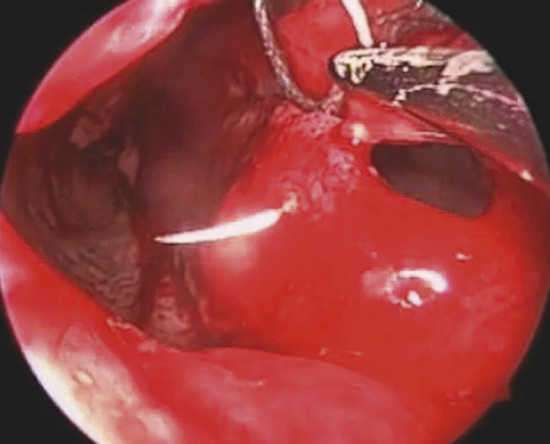

The perforation margins are then bilaterally trimmed and widely detached all around the perforation from the underlying cartilage or bone by a sickle knife to achieve a “refreshening of the edge” (Fig. 19‑1). It is important to elevate bilaterally an area of mucoperiosteum or mucoperichondrium of at least 1 cm all around the perforation.

On the other side, in oval perforation with horizontal major diameter, a horizontal incision as long as the perforation major diameter is performed by a sickle knife on nasal mucosa 1 cm to the dorsal border of septal cartilage. The mucoperichondrial flap is then elevated from the perforation margin up to the incision. The flap is thus transposed downward and the borders of the perforation are sutured together with a 3–0 Vicryl suture (Fig. 19‑3).

In the case of rounded perforations, a rotation/advancement mucoperiosteal flap is designed by a rounded incision based posteriorly on the nasal-septal artery and elevated up to 1 cm from the choana (Fig. 19‑4). Also, in this case the flap is rotated to reach the inferior border of the perforation and sutured with a 3–0 Vicryl suture (Fig. 19‑5).